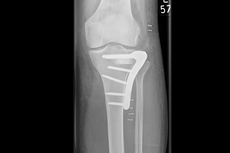

Kniegelenks-Verletzungen

Die Basisversorgung von Frakturen, die arthroskopische Chirurgie und die Fraktur-Endoprothetik, einschließlich des Teilersatzes des angrenzenden Oberschenkelknochens, gehören zum Repertoire der Klinik. So ist es uns möglich, über die Spezialisierung der Standorte unserer Klinik auch komplexeste Knieverletzungen auf höchstem Niveau zu versorgen.